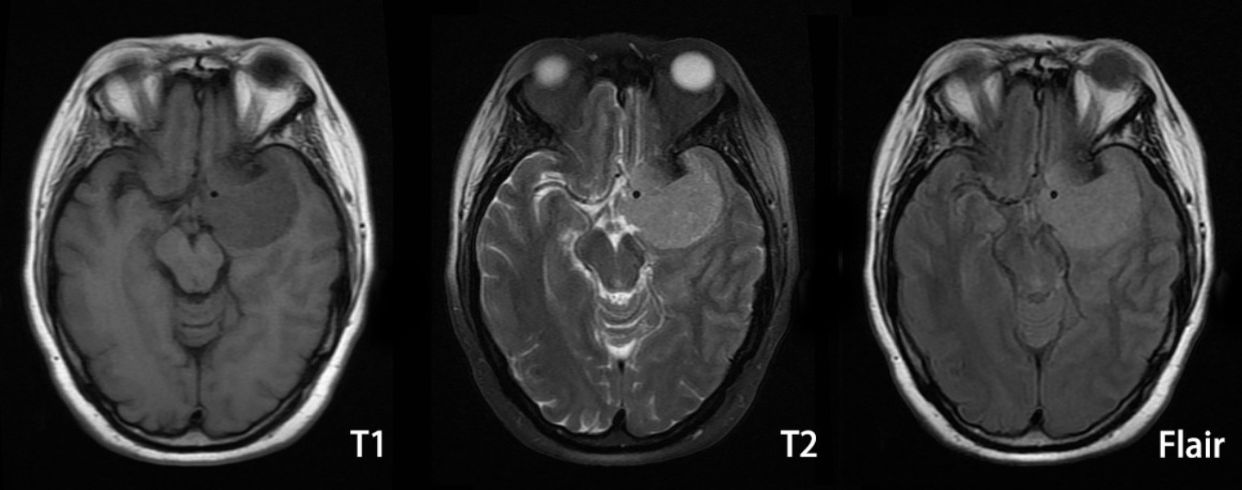

MRI检查: